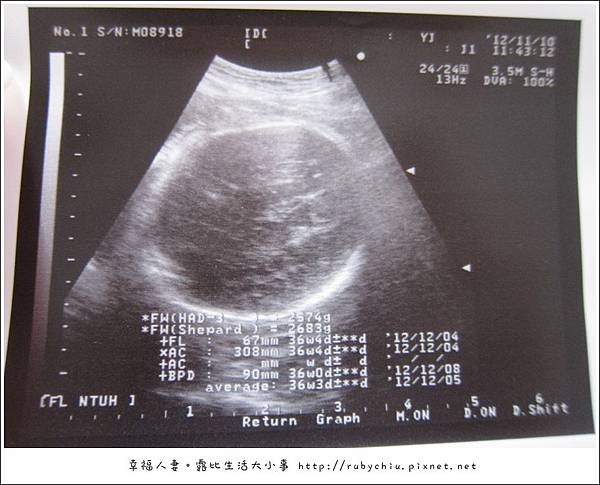

先來看看產檢影片唄!

這週剛好是35W+5D!

紀念品大小正常!約36W大!體重2700克!頭圍9CM嚕!

心跳正常!